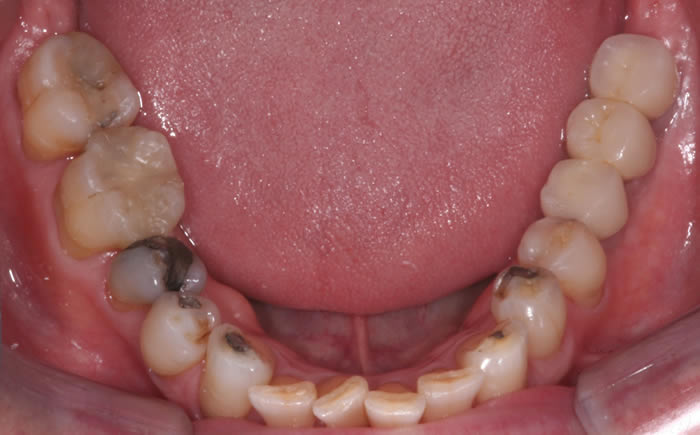

Gum disease

Case One (2 images)

Treatment of severe gum disease.